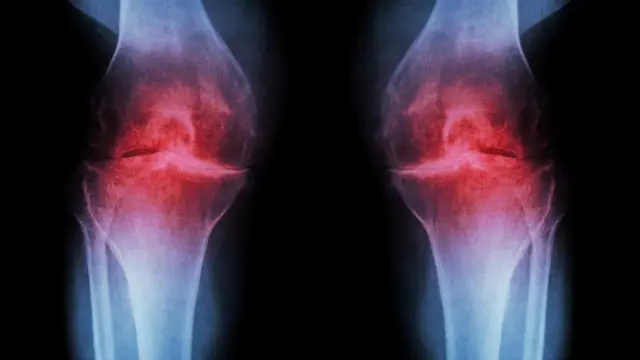

ትካል ጥዕና ዓባይ ብሪጣንያ (ኤን-ኤች-ኤስ) ጸገማት ነድሪ መላግቦ (ኣርትራይትስ) ዘለዎም ሰባት፡ ምውስዋስ ኣካላት ከም ቀንዲ መድሃኒት ክርእዩዎን ክጥቀምሉን ከምዝግባእ ሓቢሩ።

ምንቅስቓስ ዘዘውትሩ ሰባት ኣብ ፈለማ ከቐንዙዎም ዝኽእል'ኳ እንተኾነ፡ ዳሕራይ ግን በብቕሩብ ክለማመድዎን ካብ ቃንዛኦም ክመሓየሹ ከምዝኽእሉን እቲ ብመጽናዕቲ ዝተደገፈ ሓዲሽ ሓበሬታ የረድእ።

ነድሪ መላግቦ ኣዝዩ ፍሉጥ ኣብ ብዙሓት ሰባት ዝረአ ጸገም ጥዕና እዩ። ኣብ ዓባይ ብሪጣንያ ካብ 45 ዓመት ንላዕሊ ዝዕድመኦም ኣስታት 7.4 ሚልዮን ሰባት በቲ ጸገም ዝተጠቕዑ ምህላዎም እቲ ጸብጻብ የመልክት።

ነድሪ መላግቦ ብዕድመን ልዕሊ ዓቐን ርጉድን መጉዳእቲ ኣካልን ዘጋጥም ኮይኑ፡ ኣብ ገሊኦም ቅልል ዝበለ ክኸውን እንከሎ ኣብ ገለ ግን ሕብጠትን ምዕርዳድ መላግቦን ቃንዛን የኸትል።

ምውስዋስ ኣካላት ቅሩብ ክብድ ክብል ዝኽእል'ኳ እንተኾነ፡ ልዕሊ መድሃኒታት ፈውሲ ቃንዛ እቲ ዝሓሸን ውጺኢታውን ምዃኑ፡ ሊቃውንቲ እቲ ዓውዲ ይሕብሩ።

ምውስዋስ ኣካላት ንጭዋዳታት ይሃንጽ፡ ሰባት ጥዕና ዘለዎ ክብደት ኣካላት ንኽህልዎም ይሕግዝ፤ በዚ ከኣ ንነድሪ መላግቦ (ኣስትራይትስ) ምቍጽጻር ይከኣል።